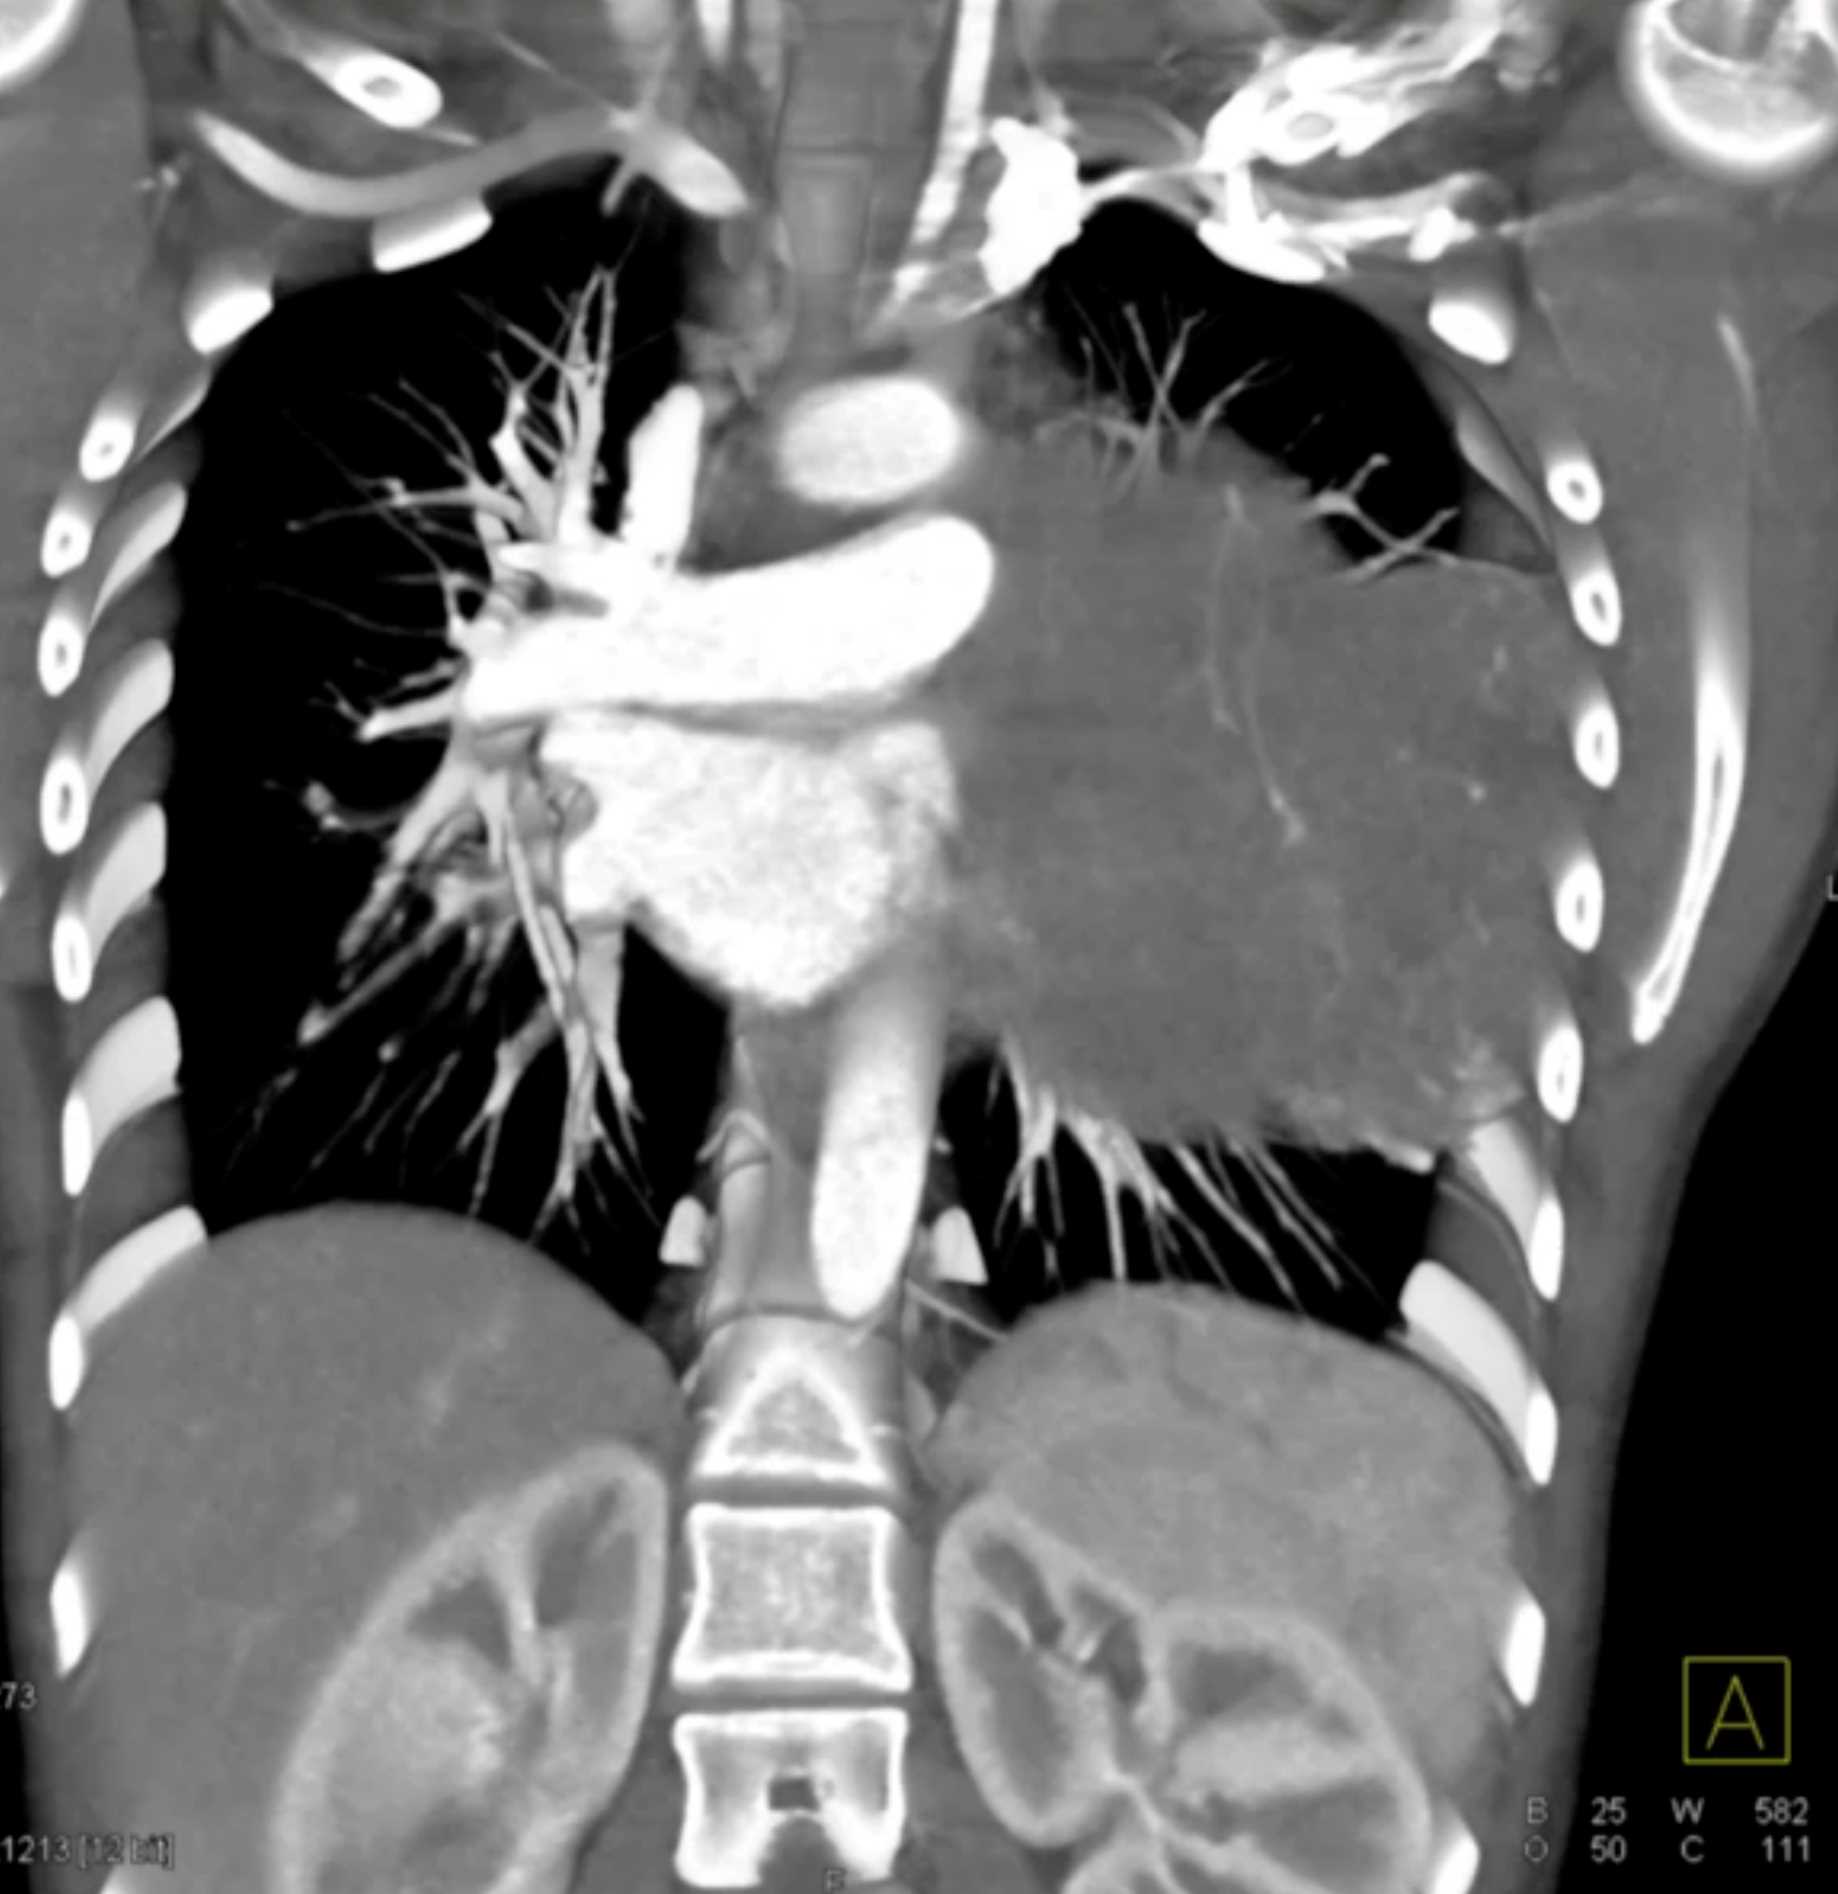

Subtle Adenocarcinoma Pancreas